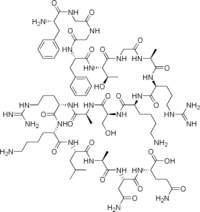

Opioid peptides

Endomorphins

Endorphins

Structures

Enkephalins

Structures

| Enkephalins | ||||

|---|---|---|---|---|

DAMGO DAMGO |

Propeptides

Others / unknown